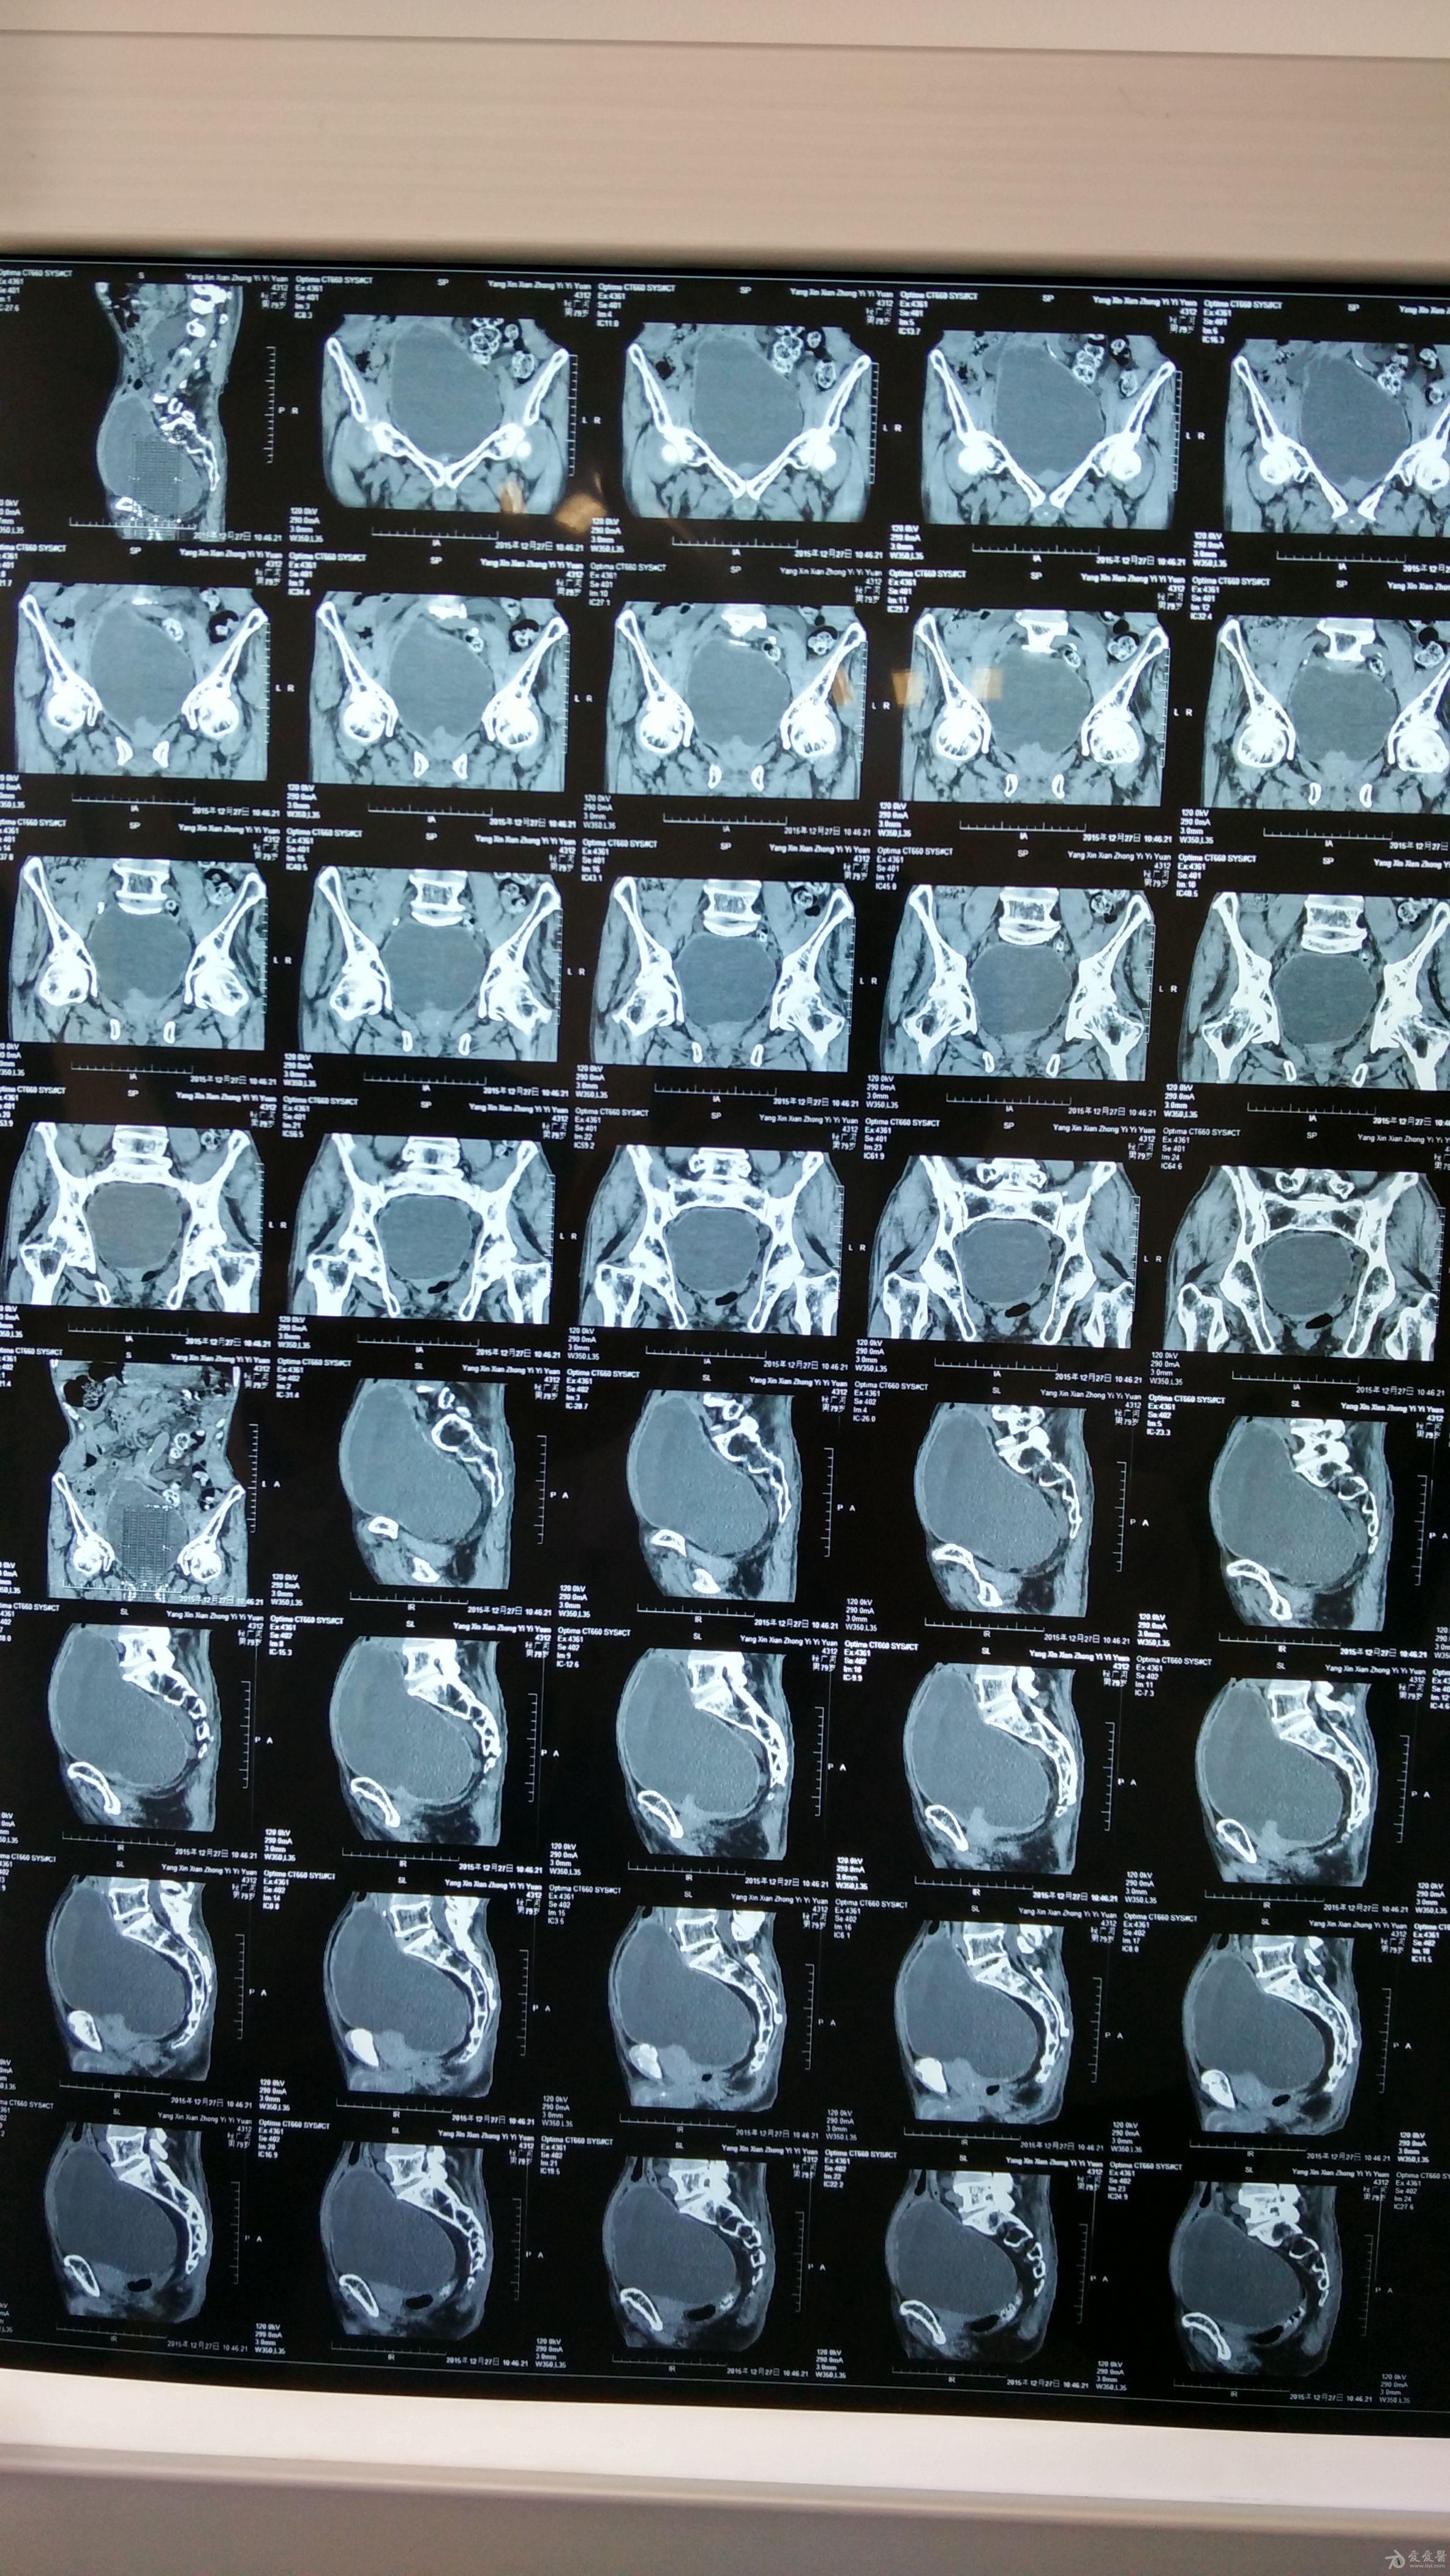

多学科联合救治危重尿毒症患者一例